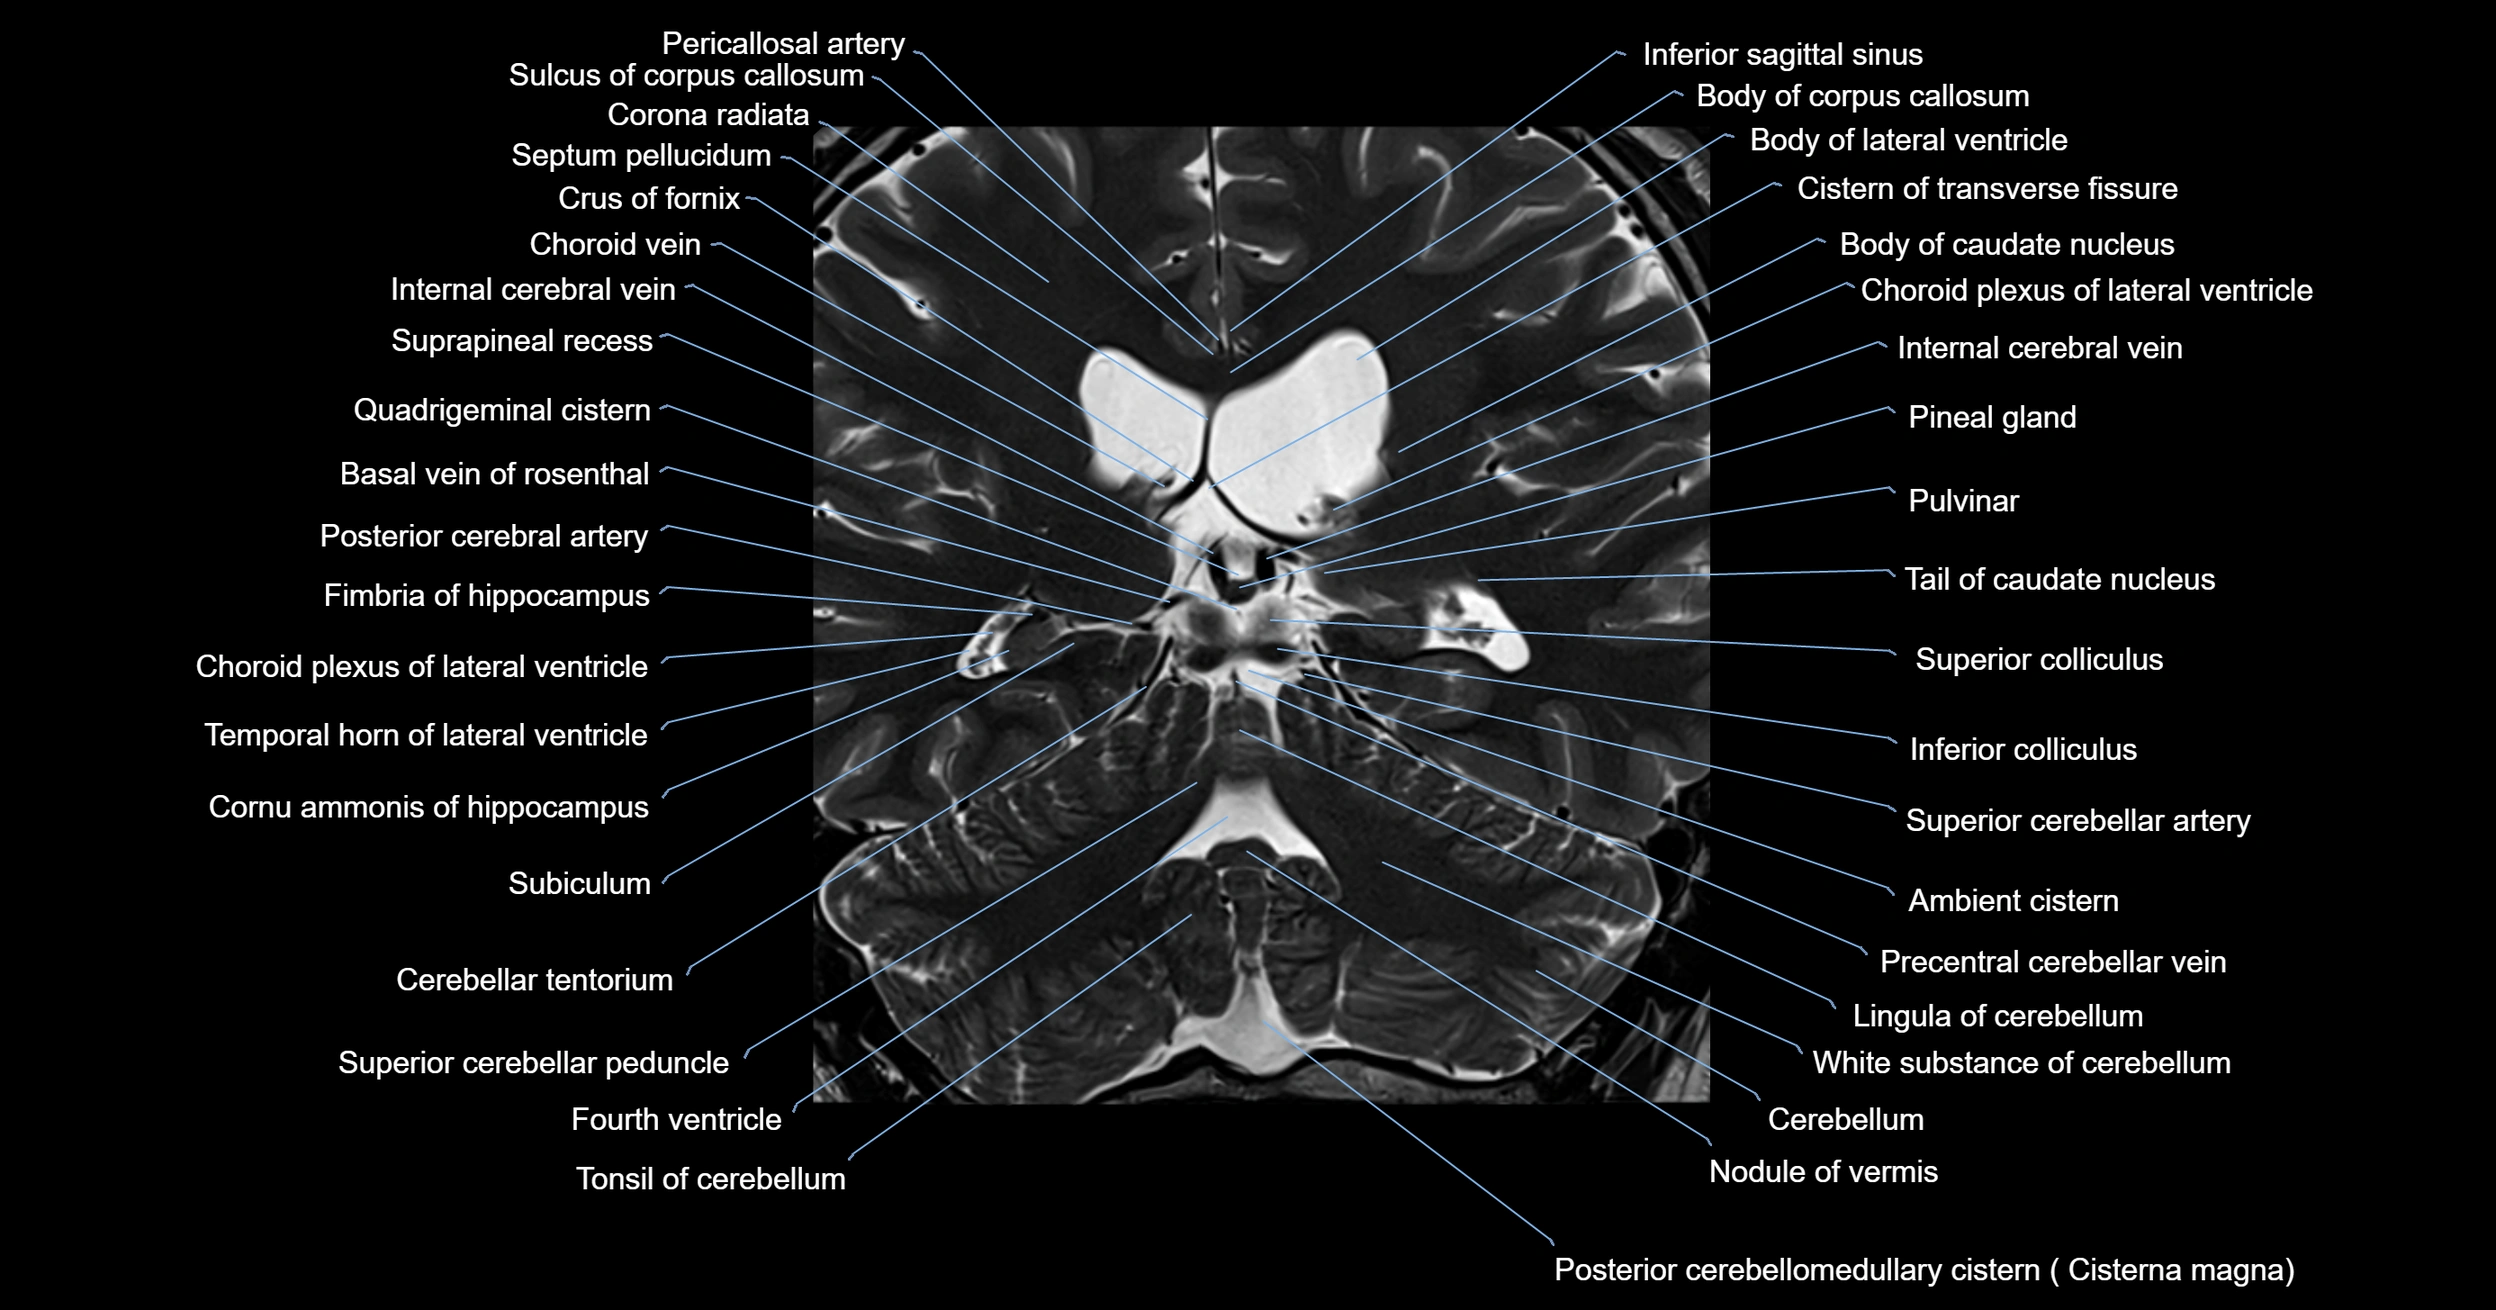

- Ambient cistern

- Basal vein of rosenthal

- Body of caudate nucleus

- Body of corpus callosum

- Body of lateral ventricle

- Cerebellum

- Choroid plexus of the lateral ventricle

- Cistern of transverse fissure

- Corona radiata

- Crus of fornix

- Fourth ventricle

- Inferior colliculus

- Inferior sagittal sinus

- Internal cerebral vein

- Lingula of cerebellum

- Nodule of vermis

- Pineal gland

- Posterior cerebral artery

- Precentral cerebellar vein

- Pulvinar

- Superior cerebellar artery

- Superior cerebellar peduncle

- Superior colliculus

- Superior vein of vermis

- Tail of caudate nucleus

- Temporal horn of lateral ventricle

- Tonsil of cerebellum

- Vermis of cerebellum